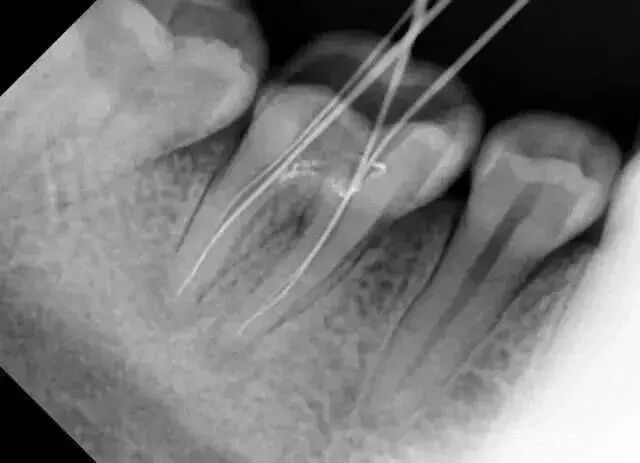

友情提示:拔智齒、做根管治療、補牙、牙周病、种植牙、牙齒矯正等都需要進行拍片。

那么常规的牙科X线檢查,輻射劑量有幾多呢?

拍一張根尖片(小牙片)的辐射剂量等于一次食下10根香蕉。

拍一张小牙片=食10根香蕉